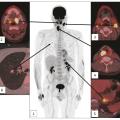

Bilan d’imagerie et orientation diagnostique des cancers des voies aérodigestives supérieures

Les voies aérodigestives supérieures (VADS) constituent la partie haute des systèmes respiratoire et digestif. Elles sont constituées de muqueuses, soutenues par des éléments musculaires complexes et des structures osseuses et cartilagineuses dont l’analyse fine est nécessaire afin de déterminer l’extension des lésions qui s’y…